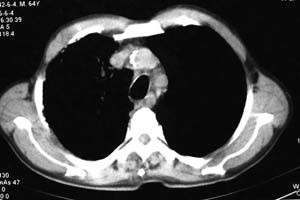

右侧胸廓略小于左侧,右肺上叶大片实变影,近肺门处密度较高,内见支气管气相,周围较淡,呈网格状,余肺野清晰,纵隔内见肿大淋巴结,右侧胸腔少量积液。临床 咳血,咳痰 发热 , 血象1.2万。

考虑大叶性肺炎。

鉴别,细支气管肺泡癌,弥漫性可有病变侵犯一个肺叶,呈炎性实变,密度偏高,可见支气管气相、蜂窝状气腔,与本例影像上不易鉴别,但临床多为咳嗽、咳白色泡沫痰,感染症状轻。

右侧胸阔塌陷,纵隔右移。右上肺大片状高密度影,沿支气管血管束走行,内见点状钙化;支气管充气征阳性,支气管呈柱状扩张;胸膜下小叶间隔增厚;右侧后胸壁内侧见带状水样密度影;纵隔淋巴结增大。

考虑:①右上叶陈旧性结核合并感染可能大。②右侧少量胸水。